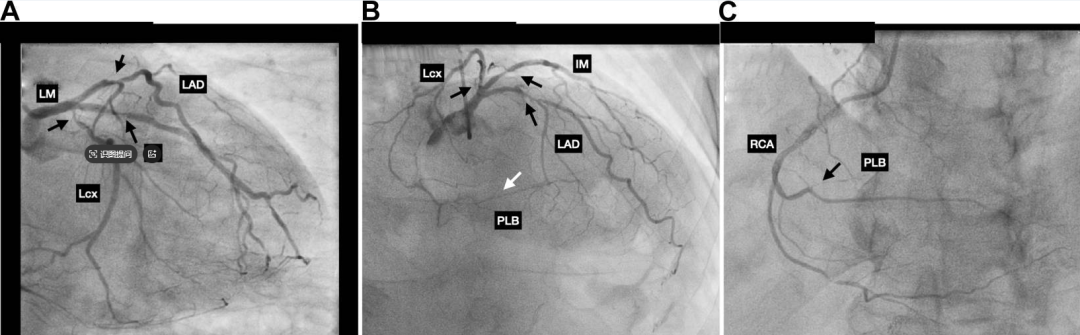

一名74岁男性因不典型胸痛就诊,拟行择期经皮冠脉造影,冠脉CTA显示严重三支冠脉病变。通过右侧dTRA进行诊断性冠脉造影,证实了前降支(LAD)近端、中间支(IM)和回旋支(LCx)近端存在严重狭窄,以及右冠脉(RCA)后侧支闭塞(图1)。

图1.基线冠脉造影显示三支病变